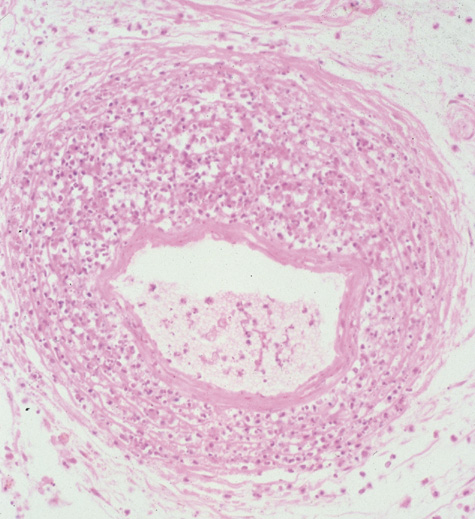

Rhinocerebral mucormycosis originates as a rhinitis, parapharyngitis, or sinusitis, and spreads by invasion of blood vessel walls, causing a necrotizing vasculitis with thrombosis of the vascular lumina and resultant infarction. The patient typically presents with unilateral orbital apex syndrome, including severe pain, visual loss, total ophthalmoplegia, corneal anesthesia, and multiple cranial nerve palsies.127 Orbital cellulitis presenting with early visual loss is one of the hallmarks of mucormycosis.72 Gangrene may occur of external periorbital tissues as well as of the hard palate and nose, and eschar-like crusting may be observed within the nose or on the hard palate (Fig. 23). Obstruction of the central retinal artery, ciliary arteries, and choroidal circulation can also be seen.124,125 Brain damage may occur because of spread of infection or infarction or occlusion of affected intracranial vessels.72

Fig. 24. Mucormycosis. A. A 72-year-old patient with acute myelogenous leukemia and invasive fungal sinusitis presented with orbital cellulitis. B. Involvement of hard palate with eschar. C. Fungi in the posterior ciliary artery.

Diagnosis is made by having a large index of suspicion and obtaining specimens of nasal turbinate, sinus, or infected orbital tissue. Large, branching nonseptate hyphae are readily apparent on hematoxylin and eosin staining or with methenamine silver staining (see Fig. 23). These hyphae can be grown on fungal culture.